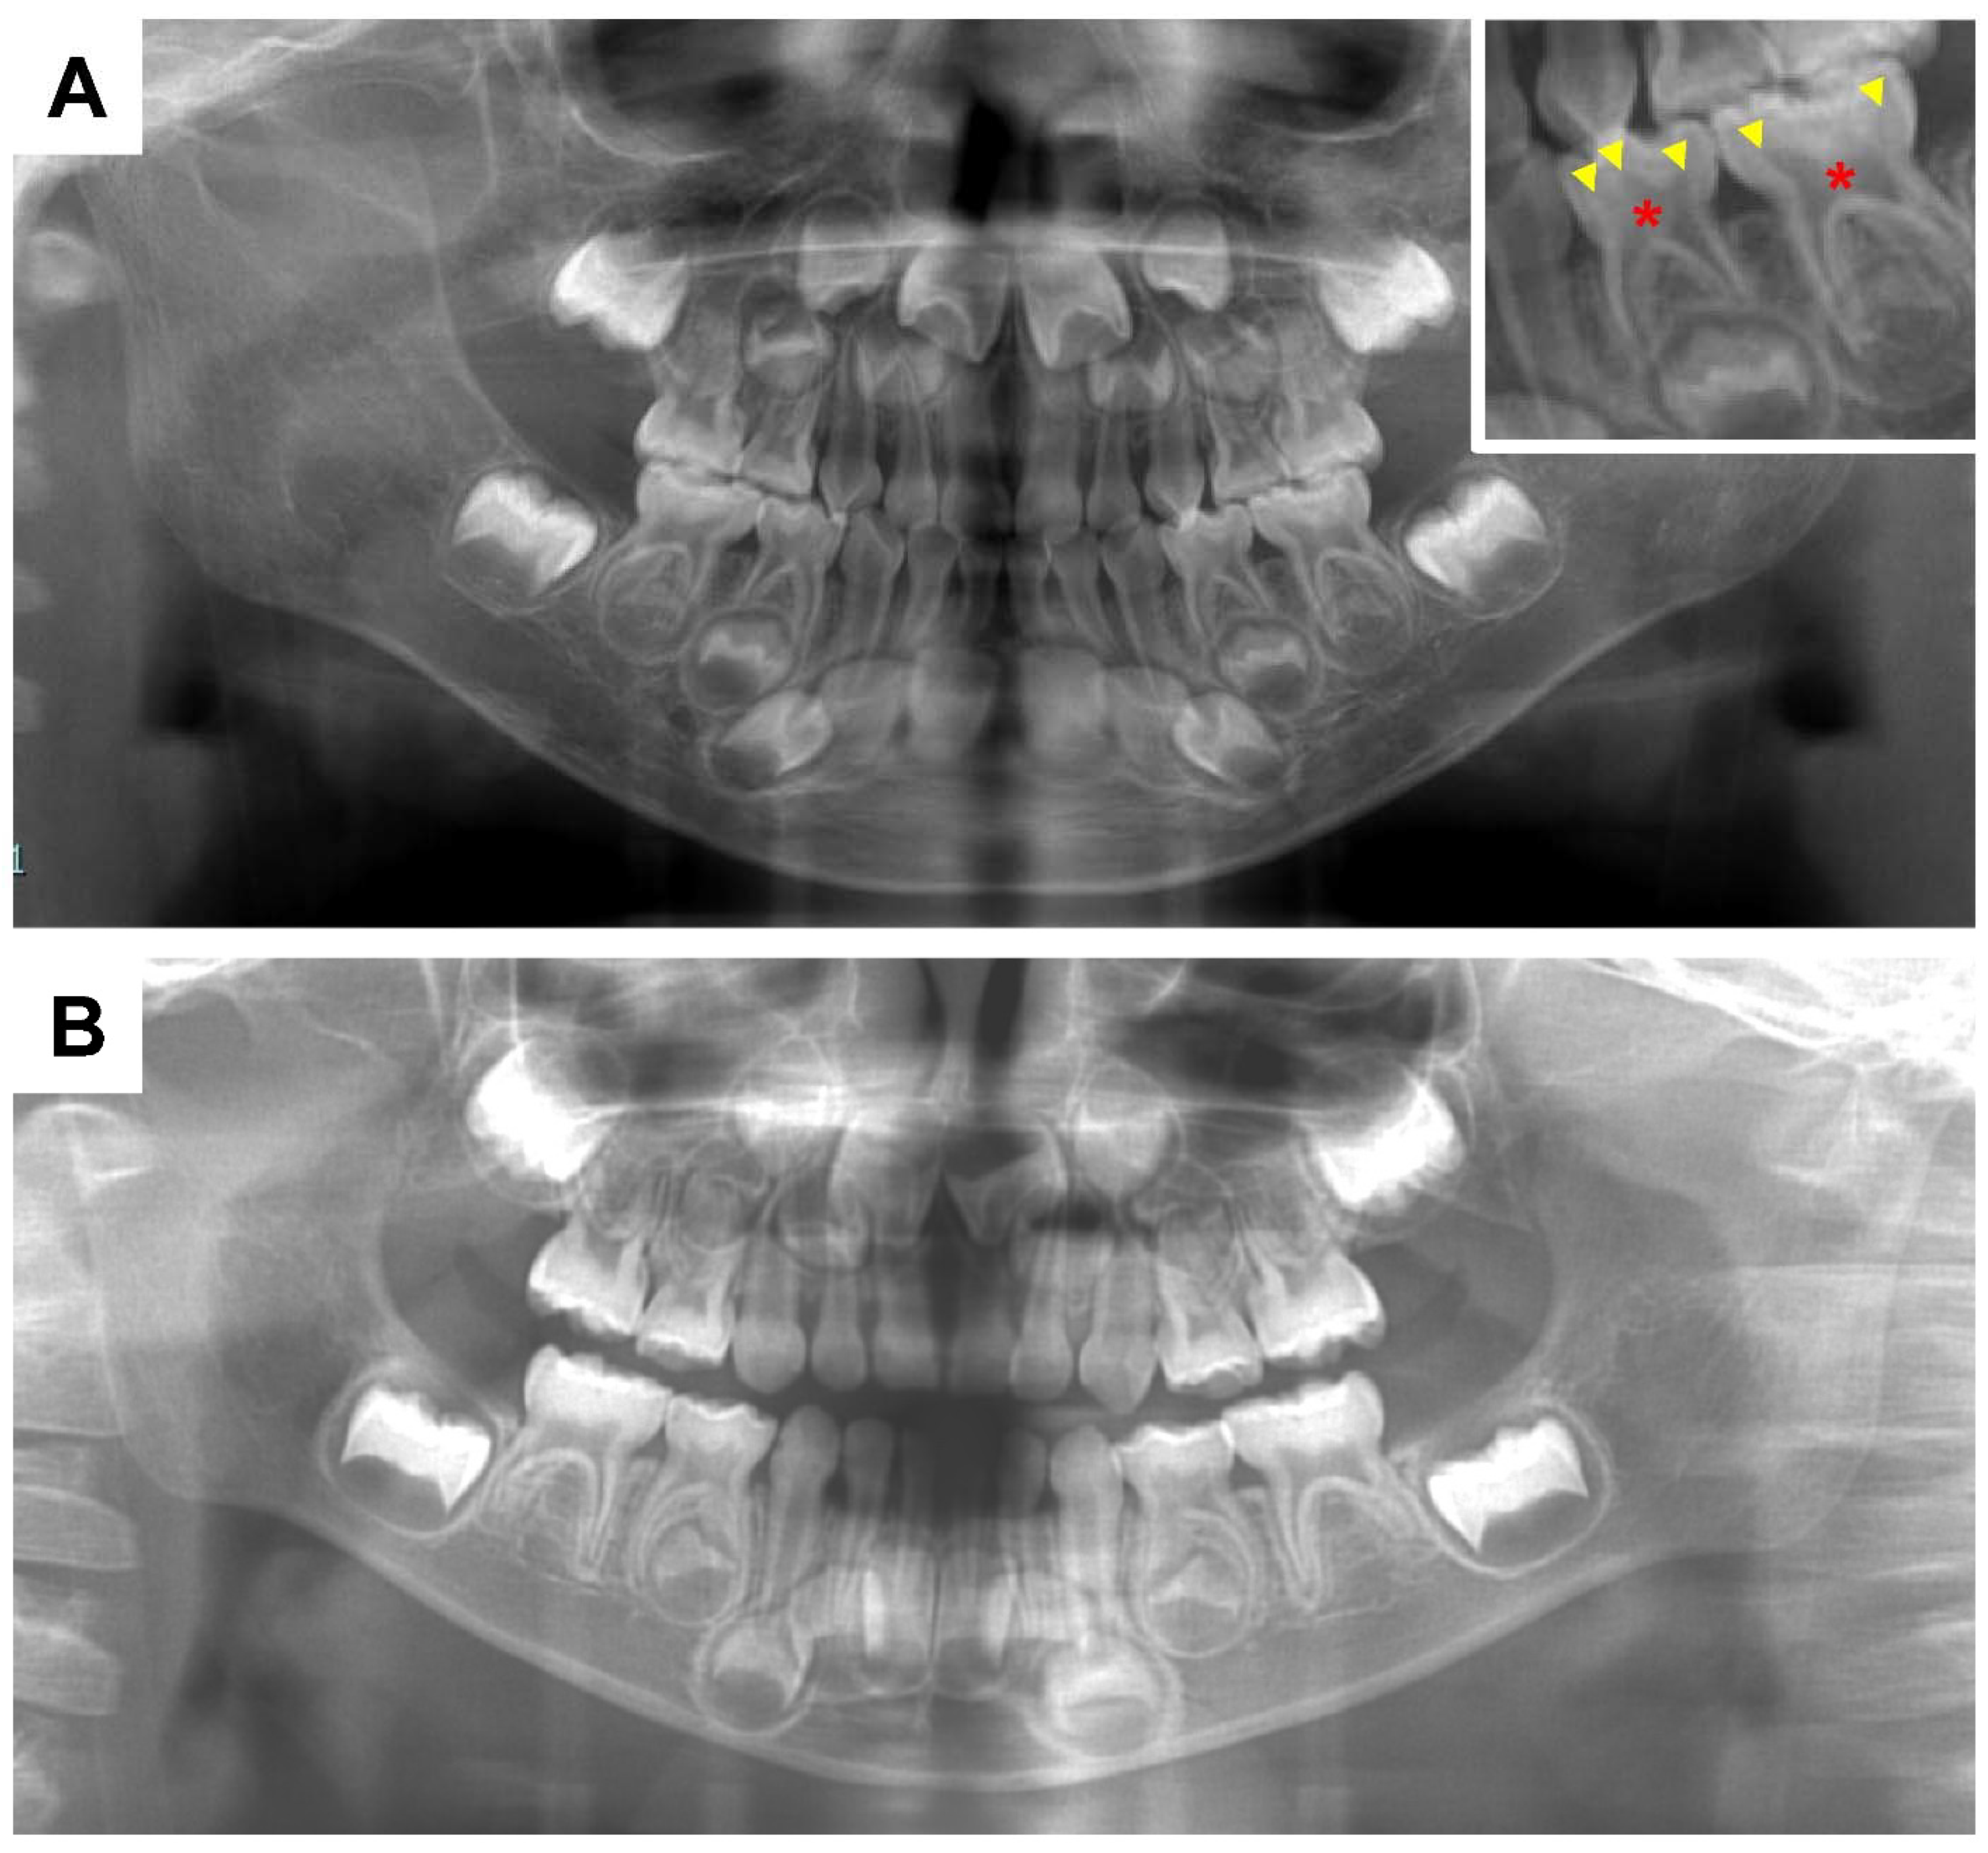

- Okawa, R.; Hamada, M.; Takagi, M.; Matayoshi, S.; Nakano, K. A Case of X-Linked Hypophosphatemic Rickets with Dentin Dysplasia in Mandibular Third Molars. Children 2022, 9, 1304. [Google Scholar] [CrossRef]